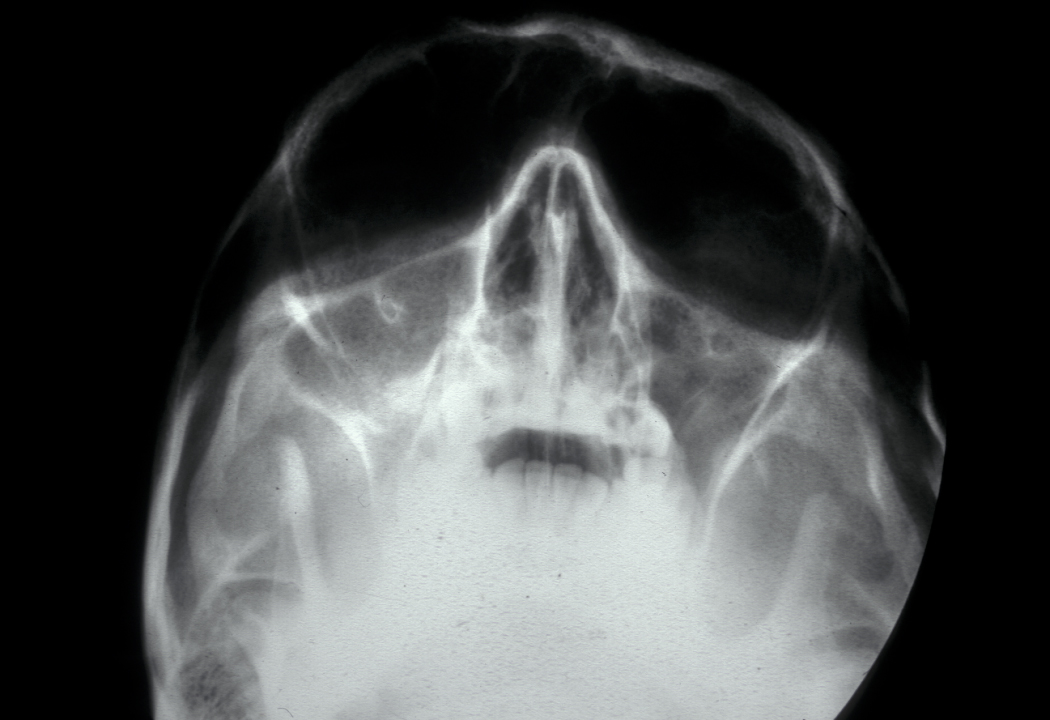

Paget’s disease of the bone is an imbalance in the bone remodelling process. Initial excessive break-down of bone tissue by overactive large osteoclasts (osteolysis) is followed by reactive chaotic increased production of bone tissue. This replacement of the normal bone remodelling process by a chaotic alternation of resorption and deposition leads to weakened, distorted bones (see Figure 5).

Figure 5: Example of the distortion of the left zygoma (cheek bone) and skull in Paget’s disease of the bone.

Bone pain and cranial neuropathies (malfunction and impairments of nerves in the skull) can occur, there may be altered sensation of the face in the affected region. Plain X-ray images show a cotton wool appearance of the affected bone; blood and urine tests show elevated levels of some characteristic markers (alkaline phosphatase and urinary hydroxyproline). Rarely Paget’s disease of the bone develops to a primary bone malignancy (osteosarcoma; see below).